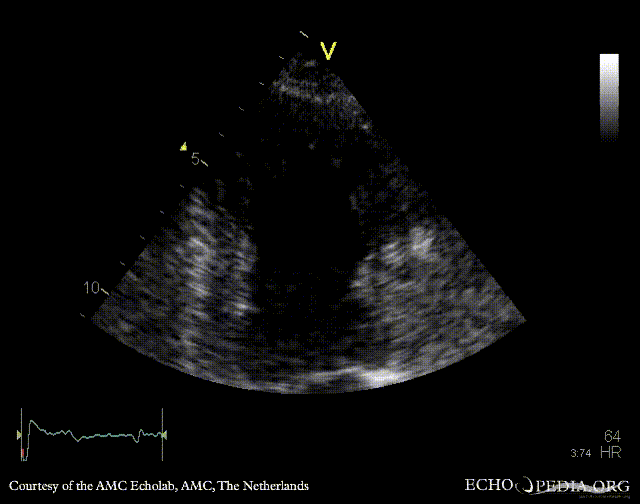

Case 112